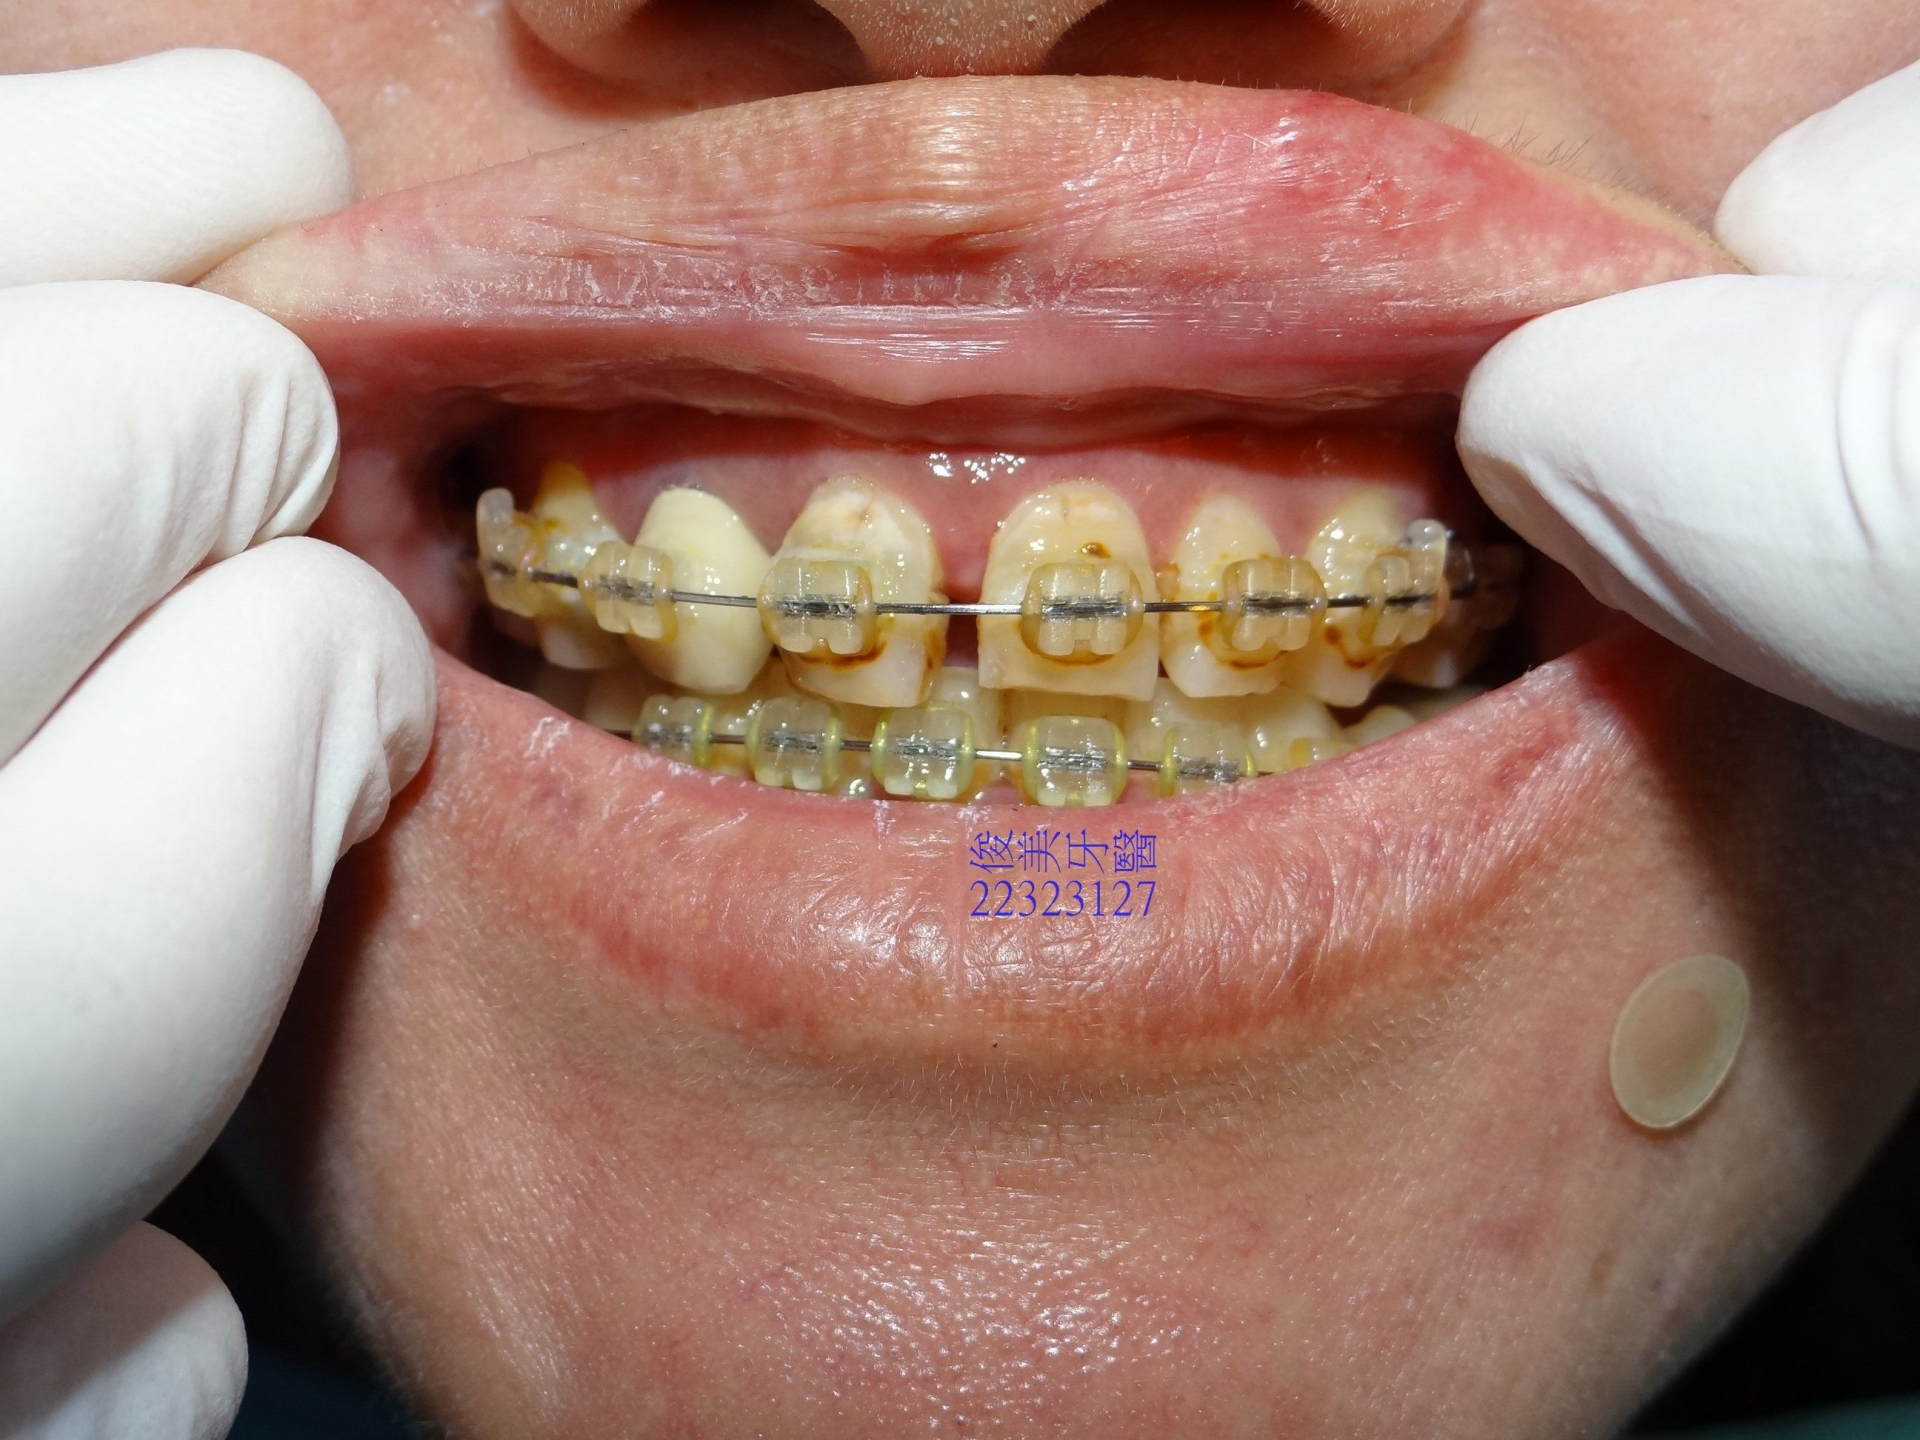

治療接近後期。

治療後,頭痛狀況,也減少許多。

臉形變v了,牙齒不再容易紅腫發炎了,好咀嚼、好清潔。